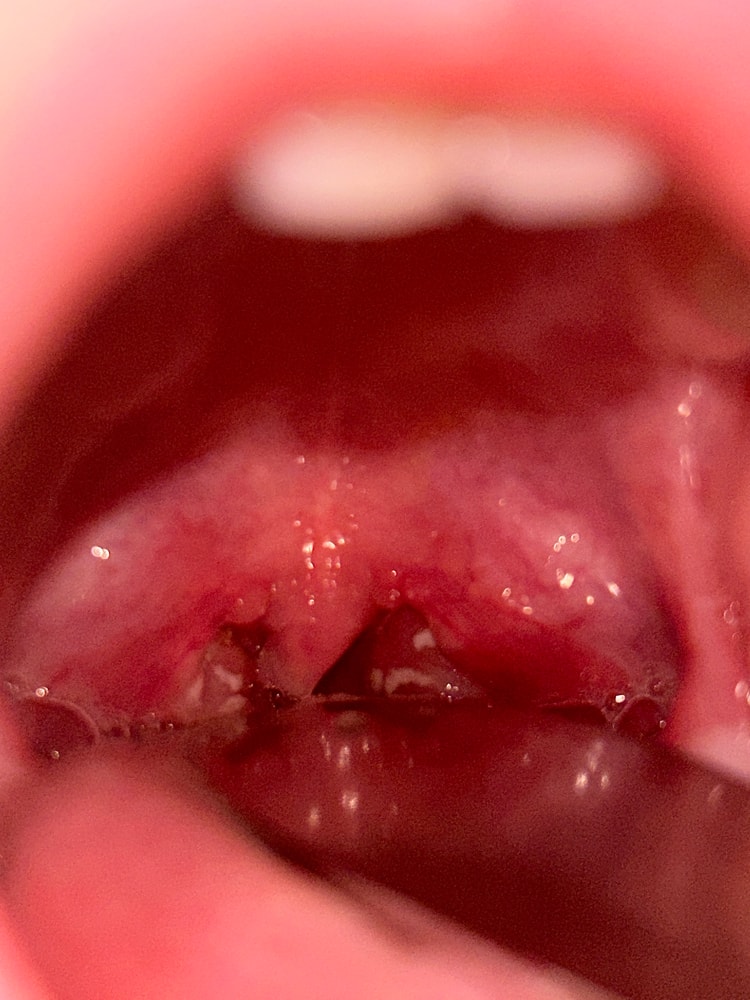

Polina, с утра говорил что устал,вечером бодрый,нос заложен,в общем то все.Я фото скинула,по состоянию миндалин похоже на бактериальную ангину.

Polina, Изображение